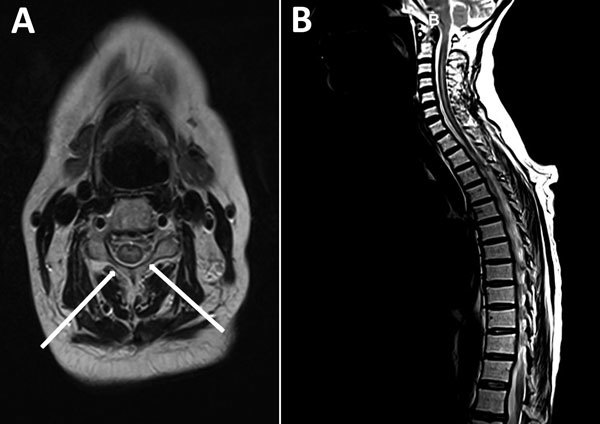

Description:In Europe in 2016, acute flaccid myelitis developed in a woman who had received a hematopoietic stem cell transplant. Enterovirus D68 viral genome was detected in respiratory and cerebrospinal fluid samples, and the viral protein 1 sequence clustered with lineage B3. Immunocompromised adults may be at risk for enterovirus D68-associated neurologic complications.